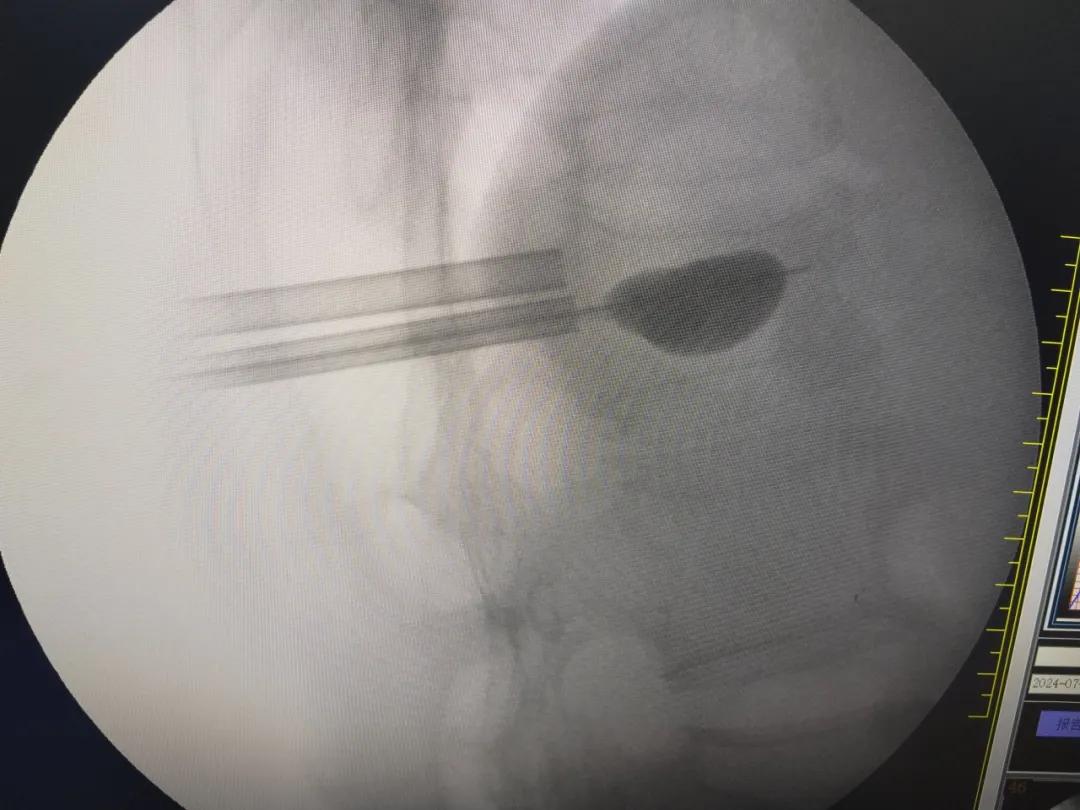

该手术在上海援青资金500万资助下的青海省内洁净程度最高的手术室内顺利开展,在C型臂X线机下对胸12椎弓根进行了精准定位标记,利用细小切口向压缩性骨折部位置入带套管穿刺针,在确认穿刺针位置满意后更换工作套管,利用球囊进行扩张后在骨折部位注入骨水泥。术中出血量仅5毫升,术后仅三天患者疼痛就明显改善,能够自由下床活动并出院,重回健康生活。